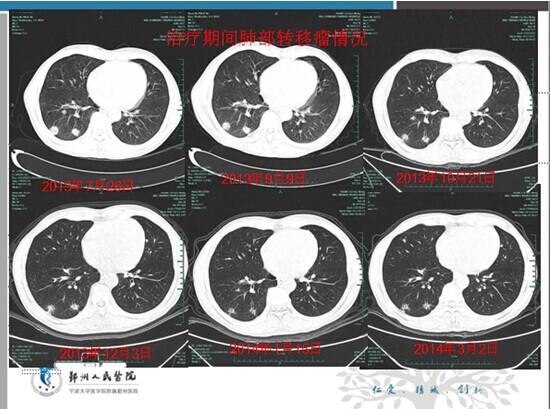

放化疗中心王锡恩主任提供的是一个成功应用赫赛汀靶向治疗胃癌的病例。患者男性,62岁;因“体检发现CA199升高1周”就诊我院,2008年11月3日在全麻下行“胃癌根治术”(全胃切除+空肠代胃ROUXEN-Y吻合,D2清扫);术后病理:贲门下中分化腺癌2.5*1.5cm,侵犯胃壁全层,小弯3/11见转移,切缘阴性。术后诊断 :pT3N1M0(ⅢA期),术后FolFox4方案化疗六周期。2010年8月胸部CT发现双肺转移之后行“DDP+S1”,“紫杉醇+S1”,“多西他赛针+S1”以及 “希罗达 +伊立替康”等方案化疗;2013年7月24日原胃癌组织蜡块做HER-2免疫组化检测,结果提示Her-2癌细胞(3+);2013年7月30开始FOLFOX6+赫赛汀(8mg/Kg首剂,以后6mg/Kg)q3w治疗3周期;因治疗过程中出现奥沙利铂过敏(低血压、晕厥),2013年10月1日改顺铂+亚叶酸钙+5-FU化疗联合赫赛汀化疗,赫赛汀连续使用12月,患者治疗效果显著,目前这个病人随访仍存活。